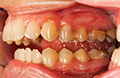

This involves ‘Before and After’ photographs of patient treatment including: implants, crowns,fillings,inlays, veneers and orthodontics. Portfolios for the practice can be produced and presented in the form of a magazine or as part of the website. The individual practice can choose how they want to display their photographic portfolios.

It is really important for patients to gain an understanding of treatment and see how things actually work. Photographic portfolios mean that patients can view real life ‘Before and After’ effects. Having a wide range of examples means that there are many different cases that patients can relate to, for example, different bites and different coloured teeth. A good dental practice updates these examples regularly. Patients can be reassured by portfolios. Portfolios can help patients to make decisions regarding whether to go ahead with treatments that they might need.

When showing a patient their detailed photographs they can understand their own problems and therefore the prescribed treatment plan can move forward with greater ease. This results in patients having a clear view and understanding of what is going on in their mouth. Dentists can also present photographs to patients to demonstrate where fillings might be necessary. Rather than just telling patients what needs to be done, Dental Photography gives dental professionals the opportunity to educate their patients.